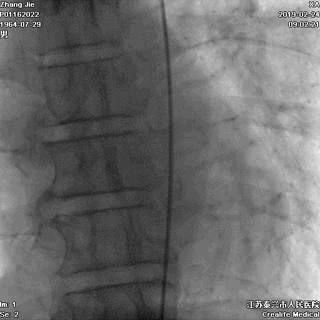

冠状动脉造影

右冠无闭塞,未见左冠的侧支